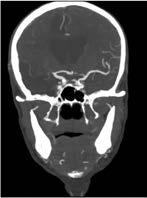

Intrakraniell: Die intrakranielle Gefäßdarstellung ist ein wichtiges diagnostisches Tool in der Therapieplanung und der Behandlung von Gefäßverschlüssen oder Gefäßmissbildungen (Aneurysmen, Angiome). Aktuell stützt sich die Bewertung von intrakraniellen atherosklerotisch-arteriellen Stenosen auf Luminalmessungen mithilfe von DSA, CTA und MRA. Gelegentlich kommt auch der transkranielle Ultraschall (TCD) zum Einsatz. Hierbei stellt die DSA weiterhin den Goldstandard dar. Die MRA wird aufgrund ihrer geringeren Invasivität jedoch wesentlich häufiger eingesetzt. Dabei ist die Timeof-Flight-MRA (TOF-MRA) die am häufigsten verwendete MRATechnik (Abb. 3a), insbesondere zum Ausschluss von Aneurysmen. Bei der intrakraniellen Stenosediagnostik mittels MRA kann infolge von Dephasierungsartefakten der Stenosegrad fälschlicherweise zu hoch eingeschätzt werden. Wegen dieser Einschränkungen hat die TOF-MRA als primäre neurovaskuläre Bildgebungsmodalität an Bedeutung verloren. Außerdem ist ihre räumliche Auflösung im Vergleich zu den anderen MRA-Techniken geringer, sodass die CTA bei der Beurteilung kleinerer Arterienabschnitte der TOF-MRA überlegen ist (Abb. 3b).

Abbildung 3a, b: Intrakranielle Gefäßdarstellung.

a: Mittels Time-of-Flight-MRA (TOF-MRA) erhobener Normalbefund (Arterien sind hell dargestellt).

b: In der CT-Angiographie zeigt sich ein Verschluss der A. cerebri media rechts.